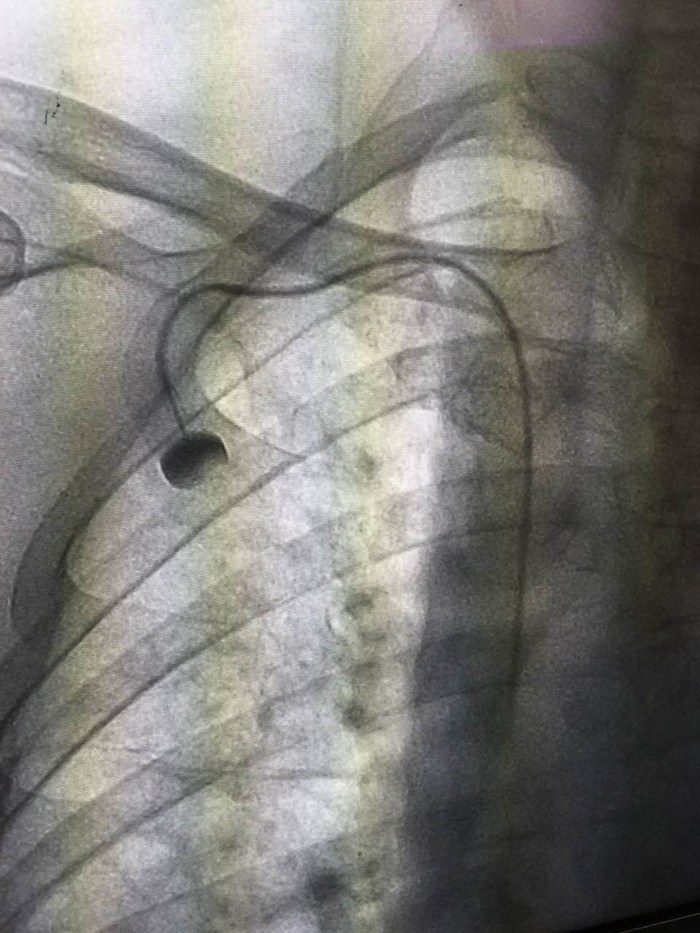

“靜脈輸液港”的X影像

??? 2月26日,我院腫瘤內(nèi)科成功開展了首例植入式靜脈輸液港技術(shù),僅在患者胸部皮膚下植入一枚紐扣大小的“靜脈輸液港”,便可解決患者因反復輸液導致無血管可扎或長期輸液導管留置的問題。

??? PORT(輸液港)是一種較新的輸液管路技術(shù),是埋植于人體內(nèi)的閉合輸液系統(tǒng),主要由供穿刺的注射座和靜脈導管系統(tǒng)組成。利用小手術(shù)方法將導管經(jīng)皮下穿刺置于人體大靜脈中,如鎖骨下靜脈、上腔靜脈,部分導管埋藏在皮下組織,將另一端的穿刺座留置在胸壁皮下組織中并縫合固定,手術(shù)后皮膚外觀只看到一個小的縫合傷口,愈合拆線后病人體表可觸摸到一突出圓球。治療時將針經(jīng)皮穿刺垂直進入到穿刺座的儲液槽,既可以方便地進行注射,也可以長時間連續(xù)輸液和采血,而且適用于高濃度的化療藥物、完全胃腸外營養(yǎng)、血液制品的輸注。輸液港植入后病人的日常生活不受限制,接受藥物治療方便又輕松,可在人體內(nèi)存留使用5年甚至更長的時間。這種技術(shù)的應用對白血病患者、惡性腫瘤患者以及長期需要打針輸液的重癥患者,尤其是此類疾病的兒童患者來說,有著重要的意義。